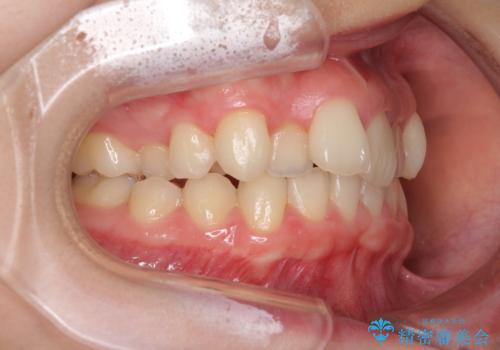

- 上顎前歯のデコボコを気にして来院された患者様です。

口元の突出感はなく、上顎のみに顕著な叢生が認められました。

上顎の左右第一小臼歯2本を抜歯し、ワイヤー装置にて歯列を整えることとしました。